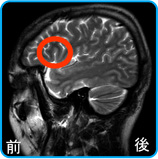

脳の左側面からのMRI脳画像

赤○は、言語野の中の伝達系脳番地の位置を示します。

ちょうど左頭部のコメカミの位置の奥に相当します。